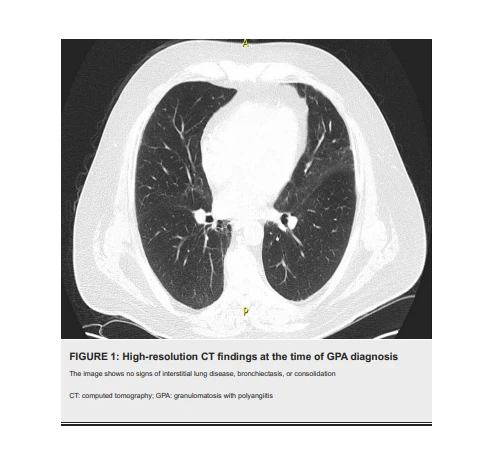

A TC basal de alta resolução (TCAR) no momento do diagnóstico de GPA não revelou sinais de bronquiectasia, consolidação ou doença pulmonar intersticial (Figura 1). No entanto, as TCARs realizadas nos dois anos subsequentes mostraram evidências de bronquiectasias progressivas, consolidações periféricas e broncocêntricas migratórias, bem como alterações fibróticas bilaterais na forma de reticulação, bronquiectasias de tração, distorção arquitetural e perda de volume (Figuras 2, 3A , 3B), que são achados atípicos à GPA pulmonar.